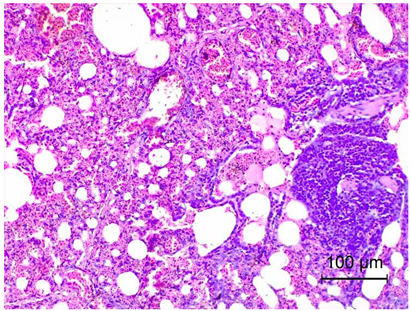

Table 4. Histopathology results of Pekin ducks with short beak and dwarfism syndrome (SBDS).

OrgansSBDS GroupNo. of Figs

LungsSevere inflammatory infiltrate forms of heterophilic and lymphocytic cells and congestion.

Exudates formation.

Applsci 14 08637 i001